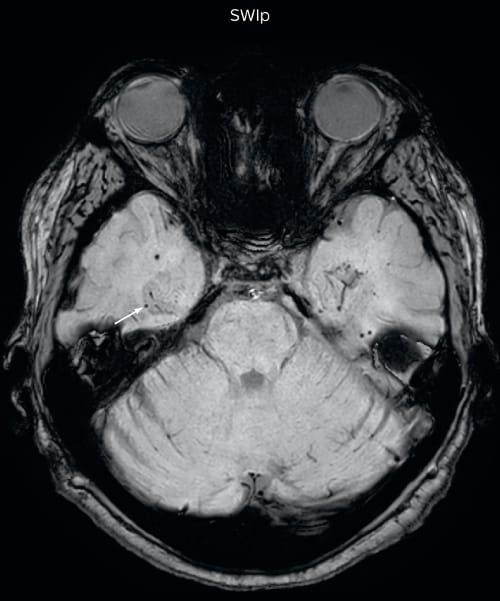

Hemosiderin foci in brain

Gradient echo imaging and SWIp are compared in a patient with radiation-induced foci of hemosiderin deposition. A greater number of small foci is seen on the SWIp image. Ingenia 3.0T

SWIp in patients with hypertension, amyloid angiopathy, trauma

The SWIp sequence offers high resolution 3D susceptibility weighted brain imaging, which helps to visualize deoxygenated blood or calcium deposits. In combination with other clinical information, it may help in the diagnosis of various neurological pathologies

“With SWIp we are basically looking for blood byproducts. It is a sensitive method for visualizing small lesions containing deoxygenated blood. In our comparison, SWIp images are vastly better than gradient echo imaging, there’s no question of that anymore.”

“We find the SWIp images very useful in three areas in particular. In patients with a history of hypertension, it offers clear visualization of hemosiderin deposition from hypertensive hemorrhages. We certainly see a greater number of foci of hemosiderin deposition on the SWIp images than on the T2* gradient echo images. In addition, it also helps us visualize amyloid depositions in patients with amyloid angiopathy.”

Dr. Nickerson mentions trauma patients are the third large area where SWIp is useful. “We benefit from SWIp in trauma patients, certainly in cases with diffuse axonal injury and shearing injuries. Our study shows that SWIp usually provides us better visualization,” he says.

SWIp in all brain exam protocols at UVM

“We switched over entirely. SWIp is now included in all our routine brain exams. We developed two different SWIp sequences: a high spatial resolution (0.5 x 0.5 mm) version that takes 5.5 minutes and our fast SWIp that takes just three minutes. Only in patients that are moving tremendously we occasionally still acquire a gradient echo sequence.”

“For us, SWIp use has resulted in more diagnostic confidence when small lesions, such as small shear injuries, vascular malformations, or minute amounts of calcification, need to be detected,” says Dr. Nickerson. “Our physicians greatly value the SWIp images. When we get patients transferred from other facilities with SWIp missing from their exam, we have several neurologists and neurosurgeons who order a new MRI exam because they want to see the SWIp images.”